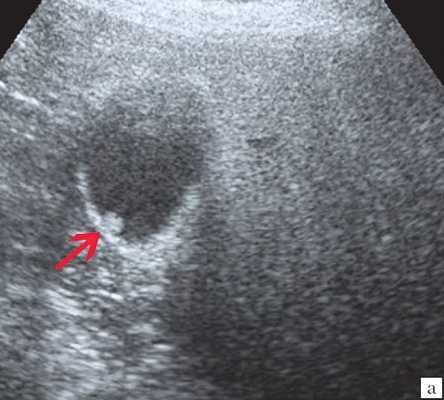

(Левый) На поперечном УЗ срезе правой доли печени определяется несколько эхогенных очагов В линейной формы, отбрасывающих «грязную» акустическую тень, что соответствует картине газа в желчных протоках.

(Правый) На поперечном УЗ срезе правой доли печени визуализируются несколько эхогенных очагов линейной формы, отбрасывающих «грязную» акустическую тень, что соответствует изменениям, возникающих при наличии газа в желчных протоках.

о Газ в просвете внутрипеченочных желчных протоков:

- Яркие эхогенные очаги линейной формы по ходу печеночных триад

- Не смещаются вниз под действием гравитации: в положении пациента на спине в желчных протоках левой доли > правой доли печени

- Отбрасывает «грязную» тень: тени с акустическим шумом, отбрасываемые отражающими звук объектами (газ)

- При больших количествах газа-артефакты типа реверберации

- Подвижность газа, лучше всего выявляемая при изменении положения тела пациента